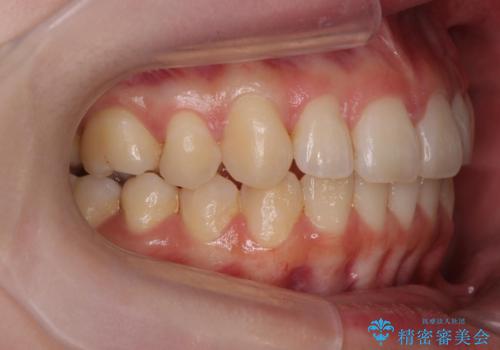

- 前歯の角度 奥歯の噛み合わせの改善をするために、矯正治療を希望され来院されました。

右側奥歯は上顎が相対的に前方に位置し(上顎前突)、そのため前歯の角度も突き出たようになり出っ歯のように見える状態でした。

マイクロインプラントを用いて、上顎奥歯を後方に移動させることで噛み合わせ・前歯の角度を改善していきます。

少し時間はかかりましたが、しっかりと綺麗な歯並びに仕上げることができ、大変喜んでいただくことができました。